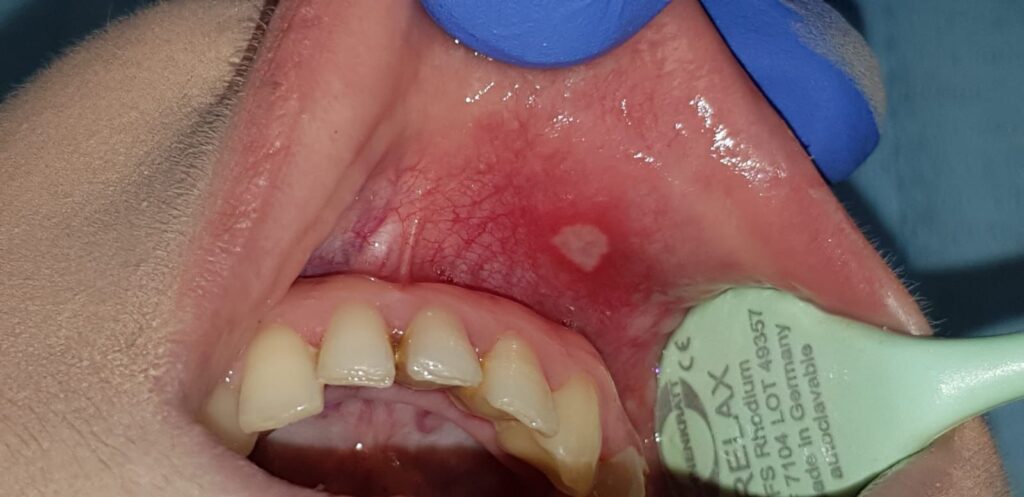

​Programul vizează identificarea timpurie a leziunilor maligne sau cu potențial malign prin evaluări clinice realizate de medici specialiști. Diagnosticul este sprijinit de tehnologia modernă VELscope, care utilizează autofluorescența țesuturilor pentru a detecta modificări celulare invizibile la o examinare obișnuită.

​Dispozitivul VELscope folosește o lumină albastră specială sub care țesuturile sănătoase emit o fluorescență verde, în timp ce zonele suspecte apar întunecate. Această metodă de diagnostic prezintă avantaje majore pentru pacienți:

​De asemenea, participarea este indicată persoanelor care observă ulcerații ce nu se vindecă în 2-3 săptămâni, pete albe sau roșii persistente și traumatisme cronice ale mucoasei orale. Diagnosticarea în stadii incipiente crește semnificativ rata de supraviețuire și poate preveni tratamente complexe precum radioterapia sau chimioterapia.